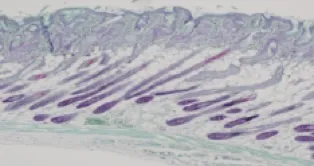

優越的組織相容度

良好的組織相容度,是注射後呈現然效果的關鍵!

在病理切片下,仙女玻尿酸顯出良好的膚相容性與耐受度,注射後與膚周圍的組織很好地融合,呈現然外觀。

注射前組織

仙女玻尿酸

他牌雙向玻尿酸